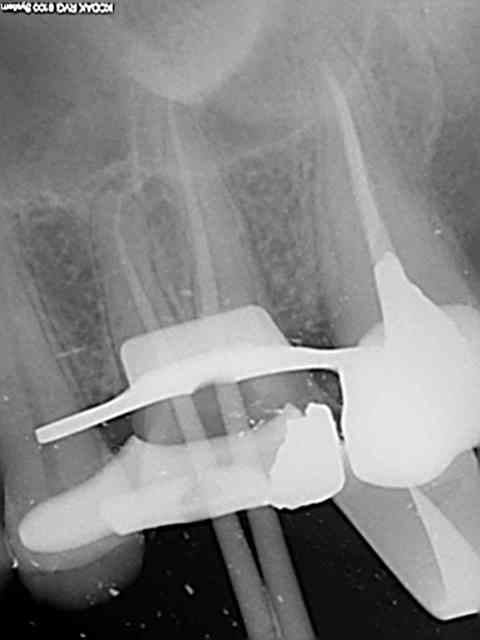

26, 60 mn endo molaire dont 30 pour trouver le canal DV (chambre calcifiée). J'ai failli jeter l'éponge mais le sx a fini par s'engager. Grosse frayeur toutefois avec le s1 sur endomaster car il a bipé d'ès son entrée dans le canal, mais c'était du à un excès d'irrigant. Ouf !

36, 30 mn endo molaire, vitesse de croisière retrouvée !))))